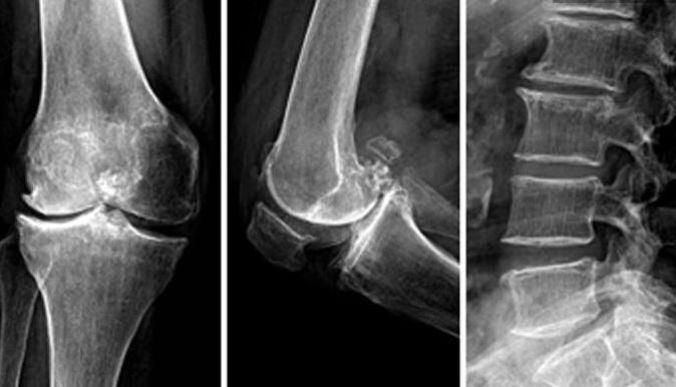

骨关节炎(OA)是发生在滑液关节的一种发展缓慢,以软骨破坏为特征的骨关节疾病,因机械性、代谢、炎症、免疫等因素功能造成,伴有相邻软骨下骨板骨质增生或骨唇形成,可伴有不同程度的滑膜炎症反应,好发于人体负重部位,如膝、髋关节、腰椎等,尤其是膝关节。

1、影像学检查

根据受累关节病情轻重程度,X线片出现的改变可进行一下分级(Kellgren分级):

0级:正常;

1级:可疑有关节间隙狭窄,似有骨赘;

2级:有骨赘,关节间隙可疑狭窄或无;

3级:有中等骨赘形成、关节间隙狭窄、关节面硬化以及关节似有变形;

4级:有大量骨赘形成、明显关节间隙狭窄、关节面严重硬化以及关节变形。